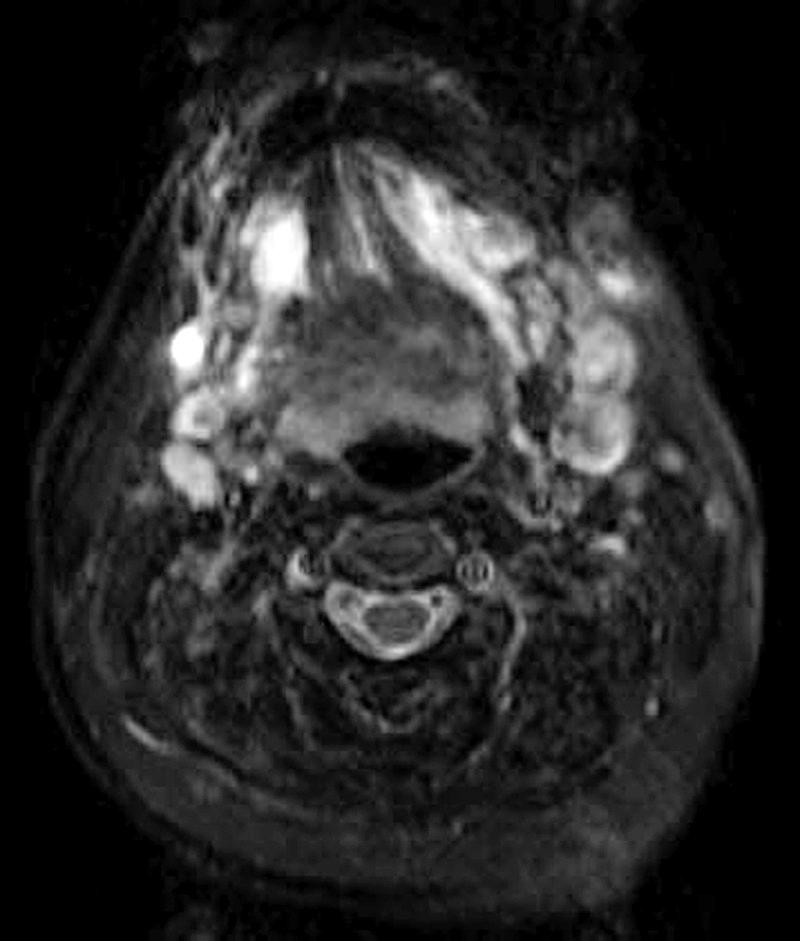

Venous malformations of the head and neck are congenital lesions that grow steadily without spontaneous regression. We describe the management of a 47-year-old woman with an extensive subcutaneous venous malformation of bilateral submandibular regions and the entire tongue, refractory to multiple surgical excisions and percutaneous sclerotherapy sessions. The tumour lacked prominent feeding arteries for embolisation, but maintained high blood outflow via a few substantial venous branches. Sclerotherapy to the lesion was prevented by major communicating branches from the mass to the internal jugular vein bilaterally. Our approach entailed direct surgical access to the malformation, ligation of these communicating veins and intraoperative sclerotherapy with ethanol injection into the vessel stumps.

头颈部静脉畸形是先天性病变,会持续生长且不会自发消退。我们描述了一名47岁女性的治疗过程,该患者双侧下颌下区域及整个舌头存在广泛的皮下静脉畸形,此前多次手术切除和经皮硬化治疗均无效。该肿瘤缺乏可用于栓塞的明显供血动脉,但通过一些粗大的静脉分支保持着较高的血液流出量。双侧从肿块至颈内静脉的主要交通支阻碍了对病变进行硬化治疗。我们的方法是直接手术暴露畸形,结扎这些交通静脉,并在术中进行硬化治疗,向血管残端注射乙醇。